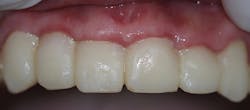

A 32-year-old male presented with having recent dental treatment abroad. Six maxillary anterior teeth had been individually crowned (figure 1).The patient’s chief complaint was severe pain in this area. He was unable to consume hot or cold food and drinks and could not use the teeth for incising. A radiographic exam revealed grossly overcontoured crowns, poorly fitting margins, and partially remaining cement (figure 2). The occlusion was evaluated and ruled out as the cause of pain. It was suspected after identifying the periapical radiolucency at the apex of the upper left lateral incisor that the pulps of some or all of the crowned teeth were affected.

Figure 1: Patient presentation with six maxillary anterior teeth individually crowned

Once local anesthesia was achieved, the crowns were removed. Pulp exposures were noted in all teeth, necessitating root canal therapy (figure 3). Once the six teeth had received root canal therapy, the access openings were restored with a flowable, dual-curing, nano-hybrid core build-up material (Grandio Core Dual Cure, Voco). The teeth were prepared to correct margins while respecting surrounding periodontal structures. In order to allow the inflamed soft tissue to heal, a provisional “one-unit” bridge was fabricated and allowed to remain for six weeks (figure 4). A cold-cure composite provisional material was used (Structur 3, Voco), providing an elastic phase and allowing easy removal from the prepared teeth. The high gloss offered an ideal margin for the healing of inflammatory soft tissue, and elevated compressive strength and fracture resistance meant the patient could function in the provisional for longer periods of time.

Figure 4: Provisional “one-unit” bridge